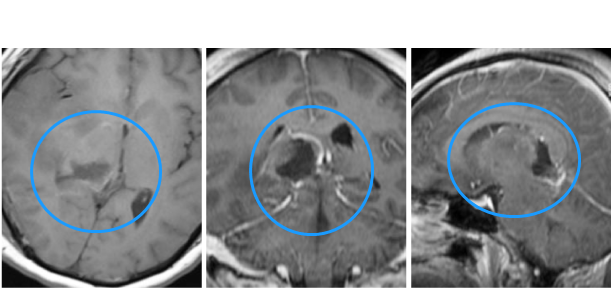

術前影像顯示:右側丘腦、右側中腦、右頂枕腫瘤占位,邊界欠清晰,周圍腦組織水腫明顯,大腦中線向左側偏移明顯。(多發(fā)性膠質母細胞瘤)

手術情況:

患者采用俯臥位,取右側枕頂骨瓣開顱,導航引導下切除右枕頂皮層下腫瘤,并進入深部切除右側丘腦及中腦腫瘤。術中功能磁共振復查,腫瘤次全切除,未出現(xiàn)手術并發(fā)癥。術后一周拔除美國醫(yī)院留置的腦室外引流管,患者無顱高壓癥狀,無再發(fā)腦積水,無再發(fā)癲癇。